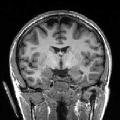

To further investigate the smoothing effect of our reconstruction algorithm, gray matter interface of the cortical surface has bee extracted using the above mentioned BrainVISA pipeline. Extracted surfaces (medial and lateral views) from mSENSE and 3D-UWR-SENSE images are show in Fig. 3 for . For comparison purpose, we provide results with mSENSE at as ground truth.

For the lateral view, one can easily conclude that extracted surfaces are very similar.

However, the medial view shows that mSENSE is not able to correctly segment the brainstem (see right red ellipsoid in

the mSENSE medial view). Moreover, results with mSENSE are more noisy compared to 3D-UWR-SENSE (see left red ellipsoid

in the mSENSE medial view). In contrast, the calcarine sulcus is slightly less accurately extracted with

our approach.

It is also worth noticing that similar results have been obtained on 14 other subjects.